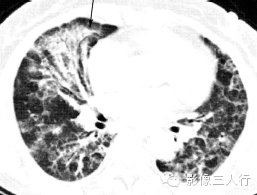

| 病毒性肺炎(图1) | 粟粒性肺结核(图2) | 细支气管肺泡癌(图3) | 肺尘埃沉着病(图4) | 肺泡蛋白沉着症(图5) | 血吸虫病(图6) | |

散在分布,6〜8mm或更小 | 分布均匀,直径1〜2mm | 分布不均,直径6〜7 mm | 分布不均,直径多为2〜5mm | 地图样、铺路石征 | 大小不等,直径多为1〜5mm |

较模糊 | 较清楚或较模糊 | 较清楚 | 较清楚 | 较清楚 | 较模糊 |

病灶密度相同,大小不等 | 病灶密度相同或不同 | 病灶密度相同,呈含气支气管征及蜂窝征 | 病灶密度不均,有钙化 | 磨玻璃密度,地图样分布和铺路石征 | 病灶密度不均,典型者可见晕征 |